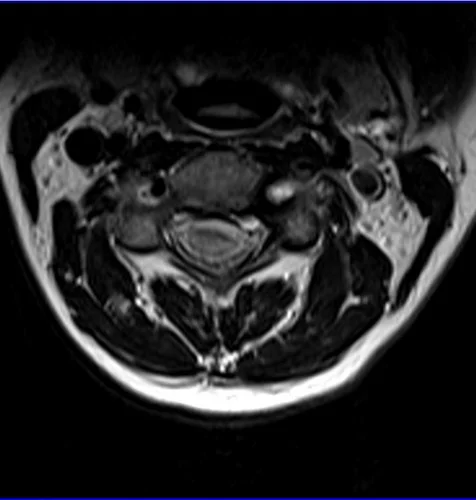

Spinal cord MRI T2 axial images of cervical cord